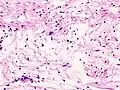

Verocay bodies are seen histologically in schwannomas.[3]